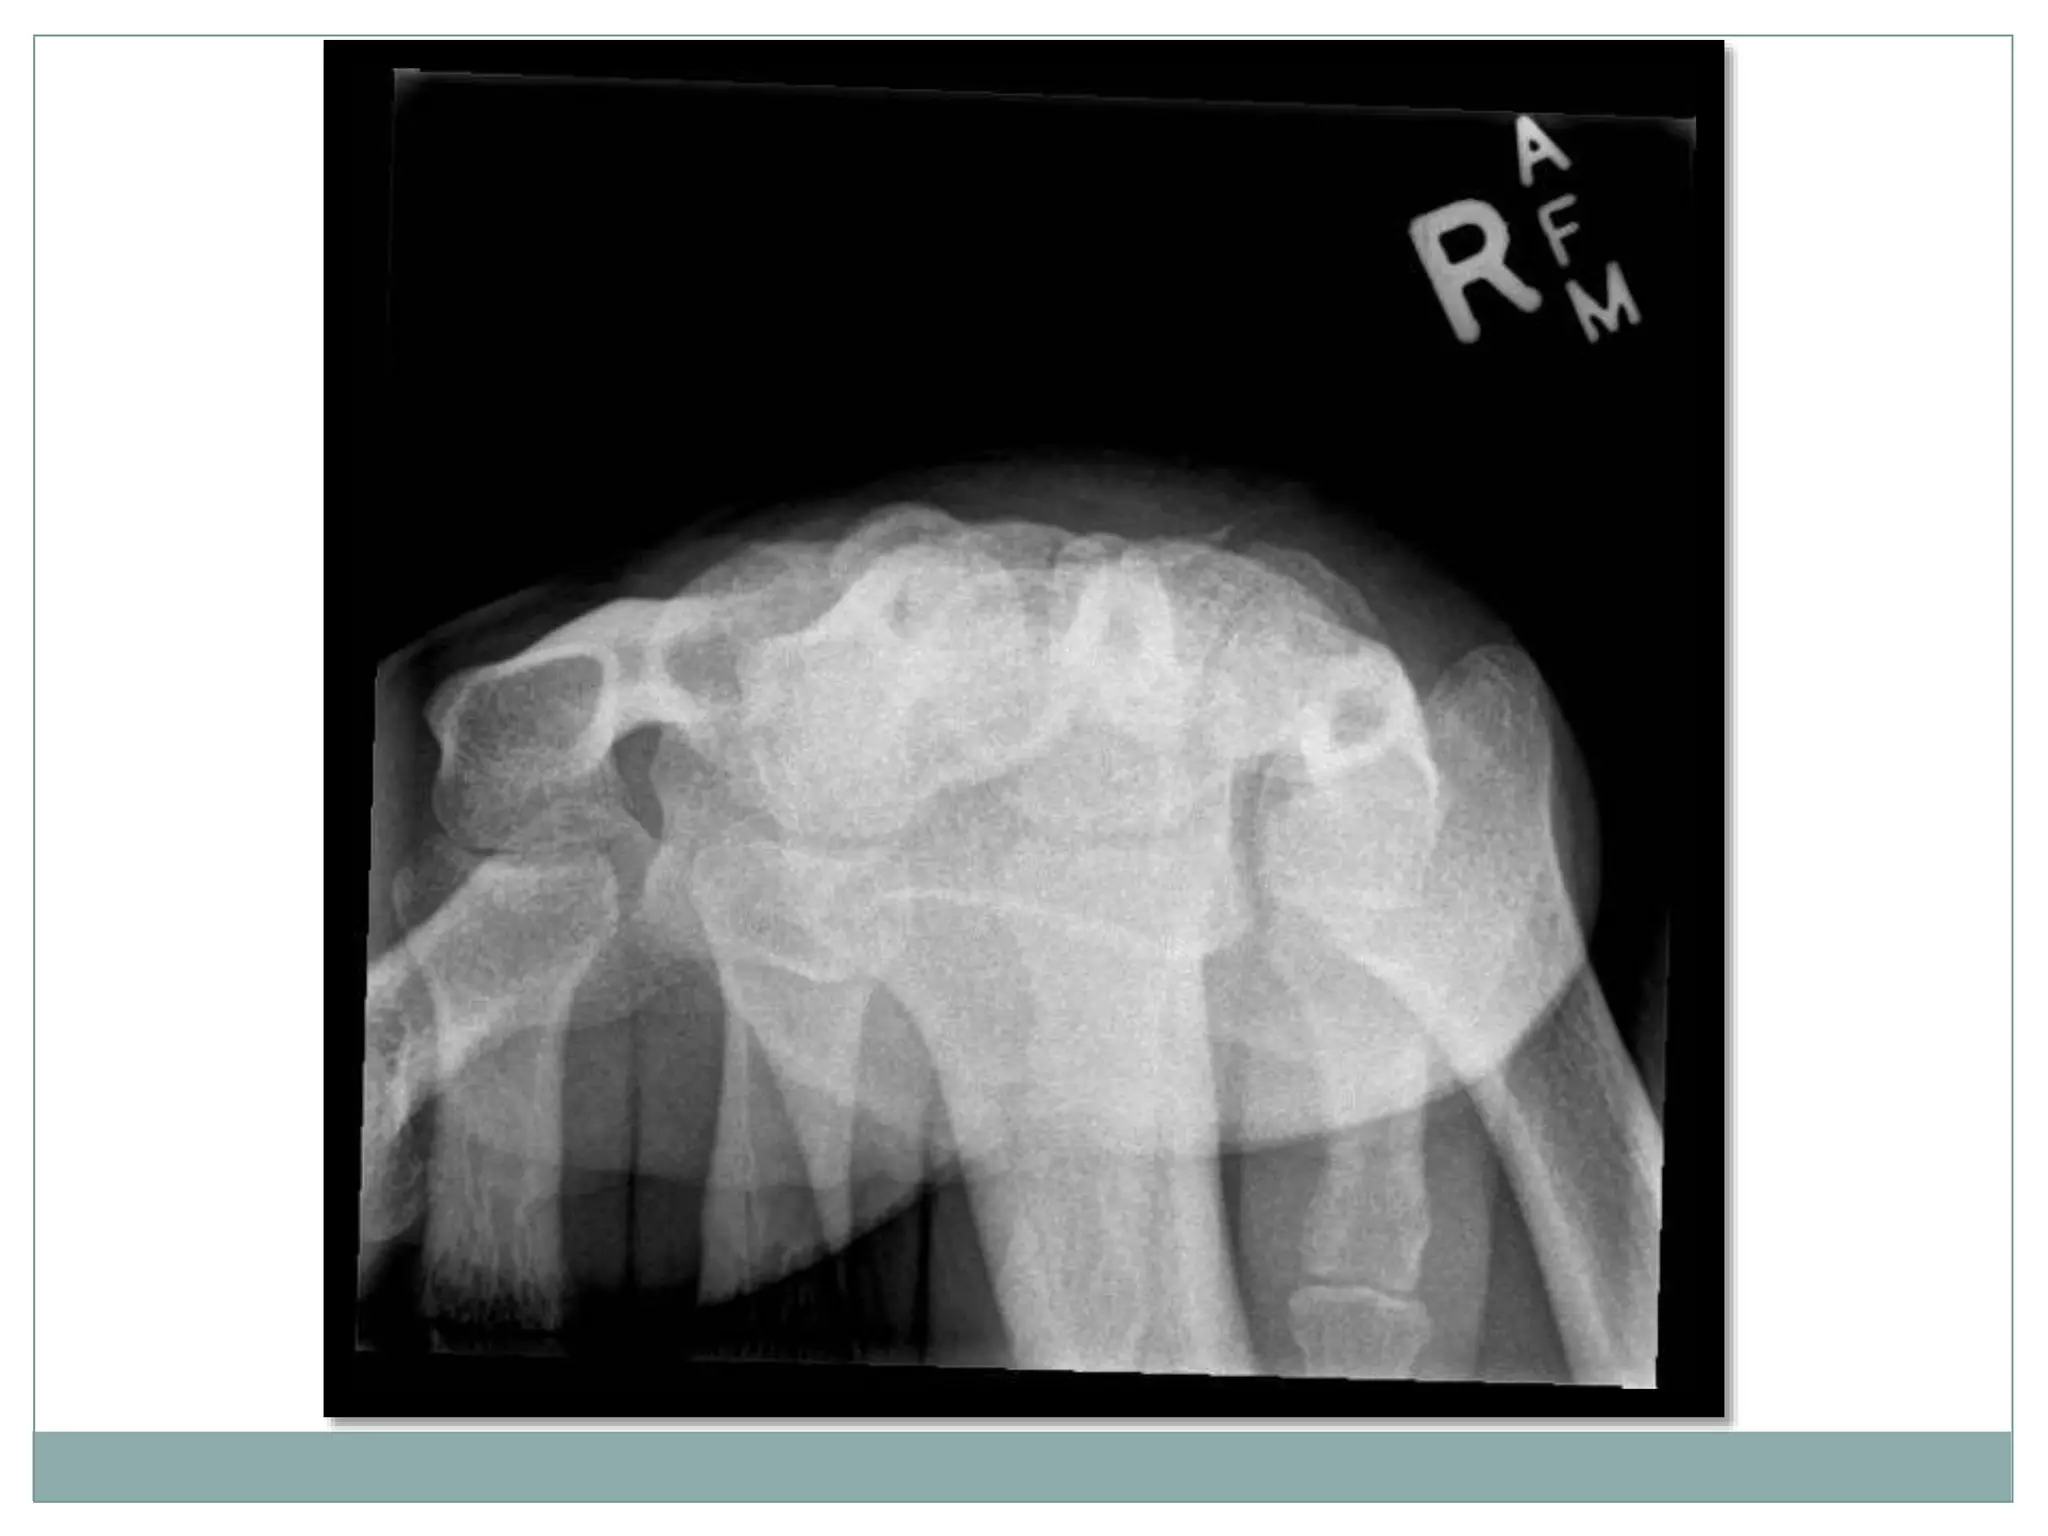

 Supero-inferior (Axial)

 Infero-superior (Axial)

The carpal tunnel view is an axial projection

to demonstrate the medial and lateral

prominences and the concavity.

 Patient is standing facing

away from the table.

 The detector is placed level

with the edge of the table

top.

 palmar surface of hand is

pressed into the detector,

with the wrist joint dorsiflexed

to approximately 135º.

 The fingers are curled

around under the table to

assist in immobilisation.

Patient Position

Carpal

Carpal TunnelCarpal Bones

Axial projection

Centring point

 Mid carpal region

 The central ray is vertical and will be

centered to the midpoint of the

dorsiflexed wrist

 Supero-inferior (Axial) Infero-superior (Axial) The carpal tunnel view is an axial projection to demonstrate the medial and lateral prominences and the concavity.

 Patient isstanding facing away from the table.  The detector is placed level with the edge of the table top.  palmar surface of hand is pressed into the detector, with the wrist joint dorsiflexed to approximately 135º.  The fingers are curled around under the table to assist in immobilisation. Patient Position

Axial projection Centring point Mid carpal region  The central ray is vertical and will be centered to the midpoint of the dorsiflexed wrist Collimation  Laterally to the skin margins  Dorsal to the skin margins  Ventral to the carpometacarpal joint

Orientation  portrait Detector size 18 cm x 24 cm Exposure  50-60 kVp  3-5 mAs

The image shouldinclude the distal end of the radius and ulna and the proximal end of the metacarpals. The joint space around the scaphoid should be demonstrated clearly.

• #5 Radiograph of carpal tunnel. The carpal bones forms as a tunnel shaped shape , the carpal ligament on top.